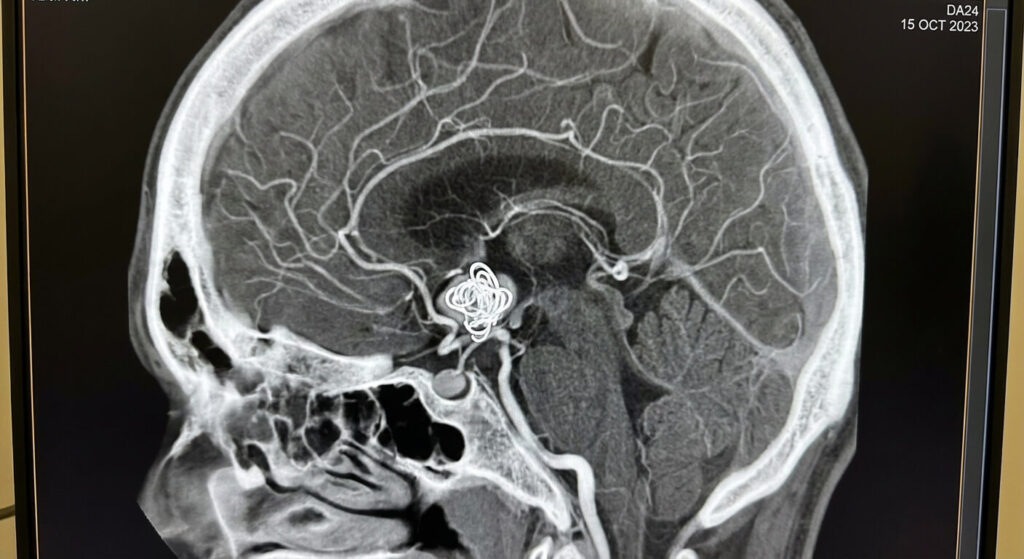

La technique de l’embolisation consiste à naviguer à l’intérieur des vaisseaux sanguins depuis l’aine ou le poignet, pour aller déposer des spirales (coils) ou de la colle spéciale directement dans l’anévrisme cérébral afin de le boucher. Bien qu’aucune incision ne soit réalisée sur la tête, le cerveau subit un stress interne important.